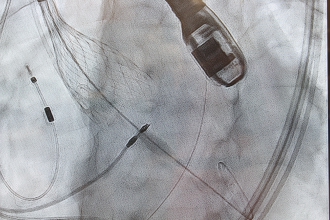

TAVI手術の様子

カテーテル的な人工弁留置の実際

1. バルーン拡張型人工弁

(1)風船カテーテルの上にかしめた人工弁を弁輪部に配置し、(2)風船を拡張して留置したうえ、(3)風船を縮小させ、回収します。

2. 自己拡張型人工弁

(1)カテーテル内に小さく収納した人工弁を弁輪部に配置し、(2)緩徐な展開により、(3)適正な位置に拡張留置します。